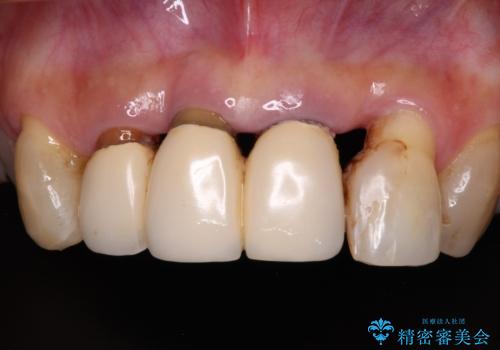

- 上顎前歯の違和感や不快感を気にして来院された患者様です。

現在のクラウンは金属の縁が見えており、歯と歯と歯肉の間に大きなスペースができていて、見た目も悪く、物が挟まったり話しにくかったりしていました。

また、前歯に抜歯が必要な歯があったため、抜歯をし、傷の治りを待ってオールセラミックブリッジにて補綴治療を行うこととしました。